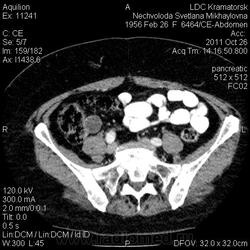

Здравствуйте! Вот уже месяц не могут поставить диагноз. Первичный очаг найти не удалось. Множественная миелома (несекретирующая?, т.к. по крови стерн. пункция не дает результата)?

Была взята биопсия с пораженного позвонка, но в материале оказалось мало клеток кости, наличие фиброзных клеток. Материал трепанбиопсии правой подвздошной так же содержал мало клеток, т.к. удалось углубиться всего лишь на 7мм (дальше сломалась игла, по словам врача скорее всего об фиброзное образ.). Можно ли по результатам КТ предложить повторный, более прицельный поиск? Что еще говорит КТ?

По имеющимся файлам-дайком я не нашла признаков опухоли. Имеется множественное остеолитическое поражение позвоночника, ребер, грудины, частично - таза. Лимфоузлы не увеличены. Тоже поставила бы на первое место миеломную болезнь. Диагностирование её не всегда простое дело. Поражена грудина и, наверное, нужно посоветоваться с онкологом (гематологом) стоит ли сделать стернальную пункцию.Советую написать в личку tatyana.